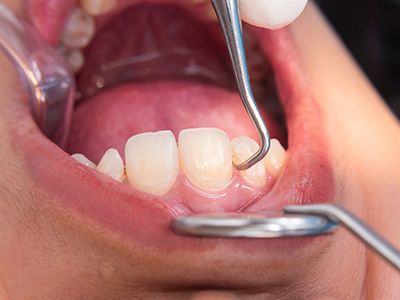

Tartar requires scaling or professional dental tools.

No, tartar cannot be removed by brushing alone. It requires professional cleaning or specialized tools.